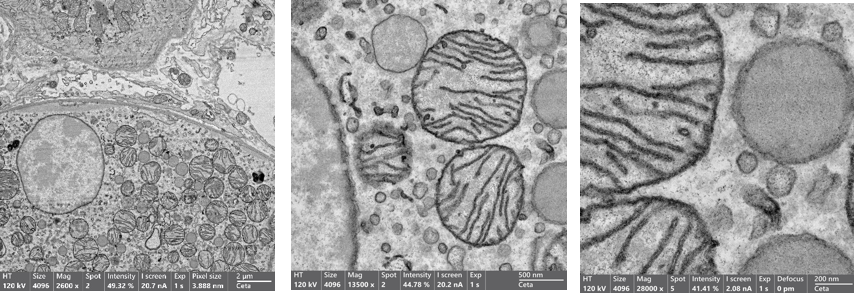

通過SEM或TEM對樹脂包埋的細胞、組織以及生物切片進行二維成像,能清晰呈現(xiàn)細胞內(nèi)精細結(jié)構(gòu)。優(yōu)化工作流程,支持大范圍組織掃描與特定區(qū)域高倍放大觀察,STEM模式為超薄樣本提供更高對比度成像(Fig.3)。

Fig.3 在低、中、高放大倍數(shù)下的肝臟組織薄片的透射電鏡成像